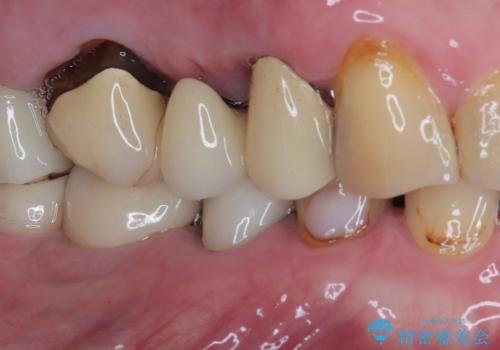

- 食事中に歯が欠けてしまったとのことで来院された患者様です。

以前詰めた材料が外れたか、歯が欠けたのかは分かりませんが、欠損している状態でした。

再度詰め物での処置を行うと引き続き欠けるリスクが高いため、高強度のフルジルコニアクラウンにて補綴治療を行うこととしました。